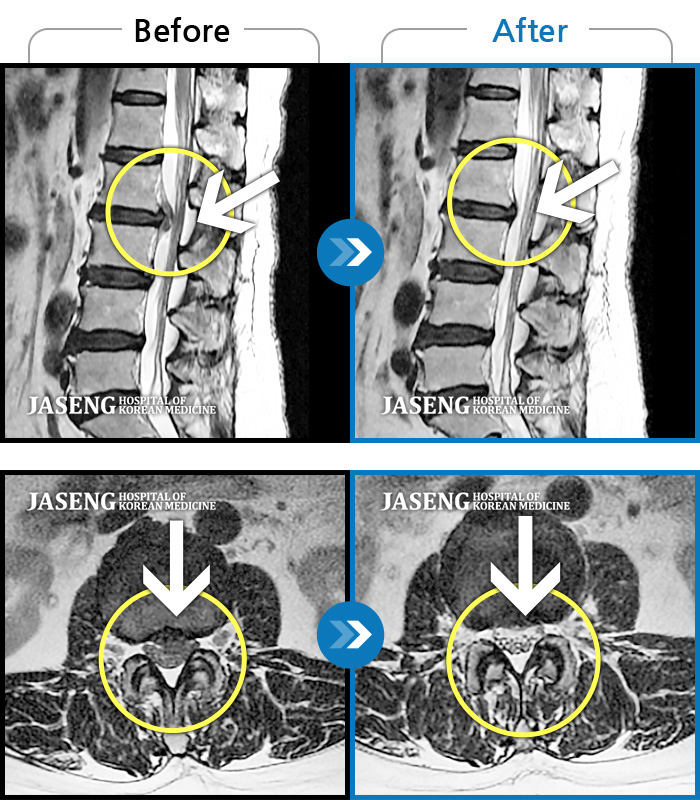

Before

After

환자에게 사전 동의를 받아 동일 조건에서 촬영되었습니다.

개인에 따라 치료 후 부작용이 발생할 수 있으니 의료진과 상담 후 치료를 진행하시기 바랍니다.

보행 시 통증 및 좌측 다리 통증

허리디스크로 인한 보행시 통증 및 다리 근력 저하